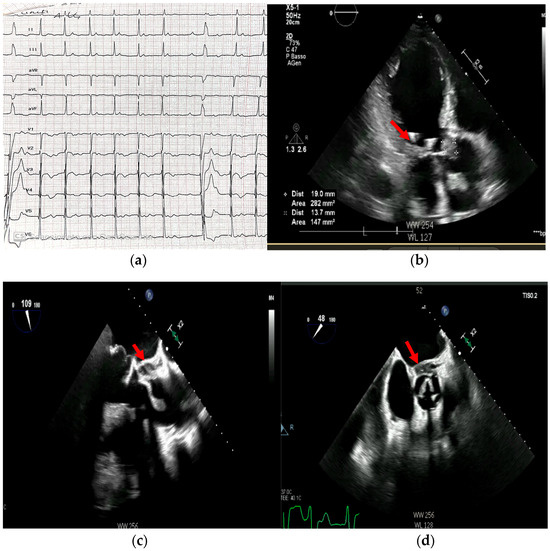

Multimodality Imaging in Infective Endocarditis: A Clinical Approach to Diagnosis

by Leonardo Brugiatelli, Francesca Patani, Carla Lofiego, Martina Benedetti, Irene Capodaglio, Pongetti Giulia, Francioni Matteo, Paolini Enrico, Nazziconi Marco, Kevin Maurizi, Furlani Giulia, Massari Arianna, Luciani Simone, Anselmi Benedetta, Gatti Chiara, Schicchi Nicolò, Fogante Marco, Tarsi Giovanni, Dello Russo Antonio, Di Eusanio Marco, Marini Marco and Fabio Vagnarelliadd Show full author list remove Hide full author list

Medicina 2025, 61(12), 2241; https://doi.org/10.3390/medicina61122241 - 18 Dec 2025

Infective endocarditis (IE) is a life-threatening condition with a rising incidence, demanding rapid and precise diagnosis. While echocardiography remains the cornerstone of initial evaluation, its limitations in complex cases—such as those involving prosthetic valves or cardiac devices—are well-known. This review synthesizes current evidence [...] Read more.

Infective endocarditis (IE) is a life-threatening condition with a rising incidence, demanding rapid and precise diagnosis. While echocardiography remains the cornerstone of initial evaluation, its limitations in complex cases—such as those involving prosthetic valves or cardiac devices—are well-known. This review synthesizes current evidence and guidelines to outline a practical, multimodality imaging approach for IE. We emphasize that integrating advanced techniques like cardiac computed tomography (CT) and [18F]-fluorodeoxyglucose positron emission tomography/computed tomography (FDG PET/CT) early in the diagnostic pathway, particularly in high-risk scenarios, significantly enhances diagnostic certainty, guides therapeutic decisions, and improves patient outcomes. A tailored imaging strategy, driven by clinical presentation and integrated within a multidisciplinary endocarditis team, is paramount for modern IE management. Full article

(This article belongs to the Special Issue Diagnosis and Treatment of Valvular Heart Diseases)

Show Figures

Figure 1